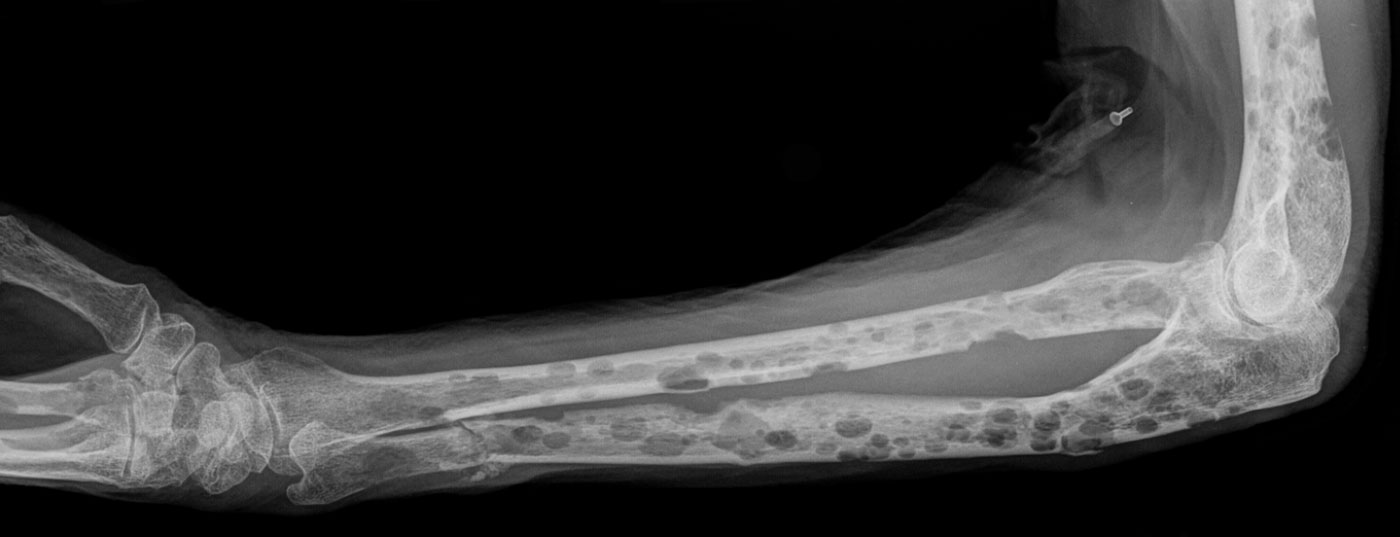

Noch immer gilt das Multiple Myelom, die pathologische Vermehrung von Immunglobulinen im Knochenmark, als unheilbar. Hochwirksame Medikamente verlängern jedoch die Überlebenszeit – in seltenen Fällen auf bis zu 20 Jahre.